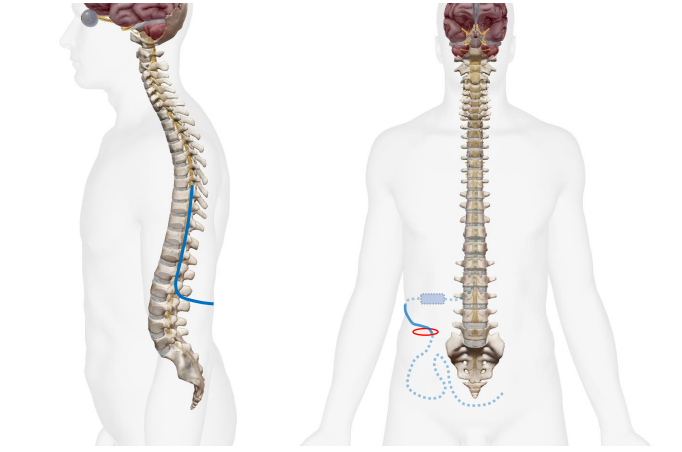

脳脊髄液を持続的に排出する機械を植え込む手術です。脳脊髄液腔から腹腔内(お腹の中)へ脳脊髄液が流れるように管を挿入します。腹腔をつくる腹膜は水をたくさん吸収するのでお腹の中にお水が溜まることはありません。管には流量を調整するバルブがついており、術後も皮膚の上から髄液の流れる量を調整できます。

背中に約3cmの皮膚切開をして、腰椎穿刺を行い、髄液腔にカテーテルを挿入し、側腹部までカテーテル、バルブを皮下に植え込みます。側腹部に約4cmの皮膚切開をし、腹腔内にカテーテルを挿入し、全てのシステムを皮下に埋めこみ、傷を閉じて終了です。